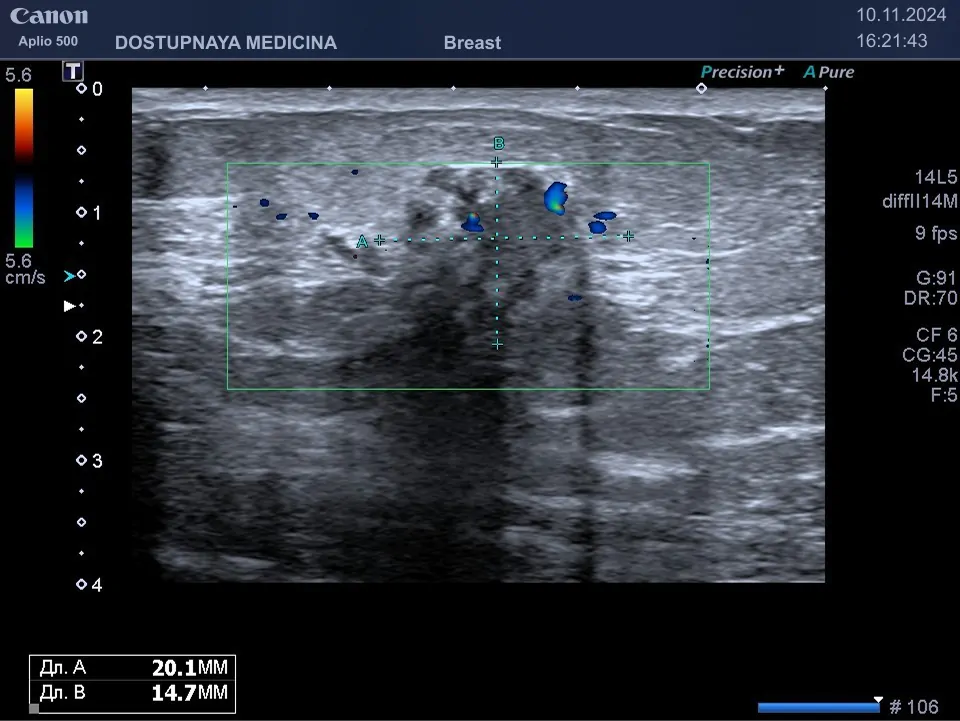

Клинический пример №2: случайно выявленное образование в молочной железе у 45-летней женщины на маммографии во время диспансеризации, направлена на УЗИ молочных желез для уточнения диагноза, при ультразвуковом исследовании гипоэхогенное образование звёздчатой формы, с нечётким и неровным контуром, с неопределённой пространственной ориентацией, с единичными локусами кровотока в режиме ЦДК, дающее дорсальную акустическую тень, категория по BI-RADS V. Злокачественный характер опухоли затем подтверждён гистологическим исследованием после трепан-биопсии.